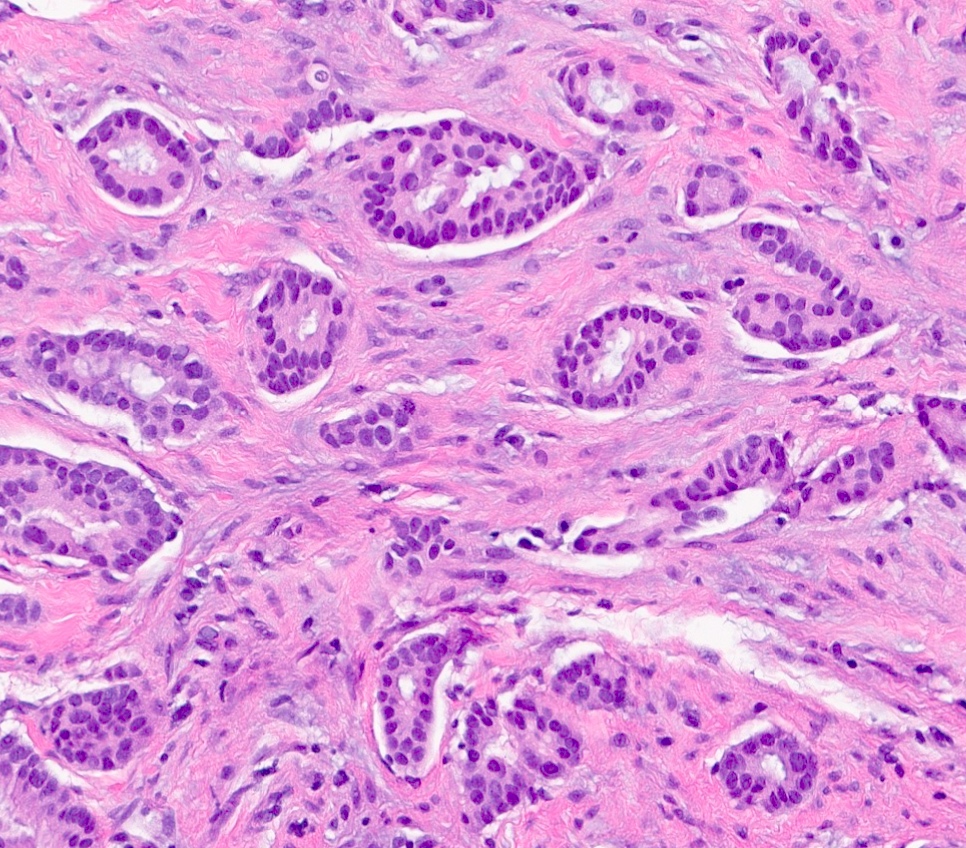

Microscopic (histologic) description

- Luminal

- Invasive ductal carcinoma, no special type (IDC, NST)

- Also tubular, mucinous, invasive lobular carcinoma (classic and variants), cribriform, invasive carcinoma with neuroendocrine differentiation, micropapillary, some apocrine / oncocytic carcinomas

- Luminal A: IDC, NST, grade 1 or 2

- ER positive, PR positive, HER2 negative, Ki67 low

- Luminal B: IDC, NST, grade 2 or 3

- ER positive, HER2 positive (Ki67 and PR can show any degree of expression)

- ER positive, PR negative or low, HER2 negative, Ki67 high

- Luminal A: IDC, NST, grade 1 or 2

Microscopic (histologic) images

C. Luminal A. Invasive breast tumors classified as luminal A by gene expression profiling are typically low grade invasive ductal carcinomas. By definition, the luminal A intrinsic subtype shows strong expression of hormone receptors (ER and PR) and is negative for HER2 / neu overexpression and amplification. Special histologic subtypes that cluster with the luminal A subtype include tubular, mucinous and cribriform carcinomas. Answers A, B and D are incorrect because basal-like, HER2 enriched and luminal B tumors are characteristically high grade.